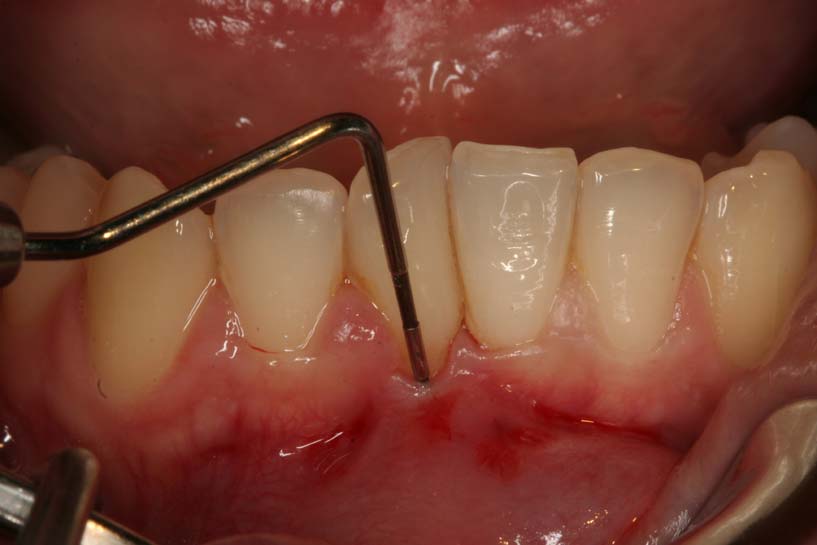

Cuando hay sarro, la mejor manera de eliminarlo es por medio de una limpieza dental efectuada por un odontólogo profesional, quien poseerá las herramientas que se necesitan para ello. Por esa razón es tan importante visitar al odontólogo de forma regular, ya que si el sarro no es eliminado exitosamente de los dientes y encías, esas bacterias que estarán calcificadas, podrán acceder a otras zonas, comprometiendo las estructuras bucales, al llegar a líneas que se encuentran debajo de la encía.

En esta etapa del proceso de acceso de la placa dental calcificada a esas zonas, se van a formar lo que se denomina bolsa periodontal, que es realmente la acumulación excesiva de bacterias a niveles subgingivales y su accionar poco a poco va a ocasionar daños graves en el hueso alveolar, que es el hueso al que están adheridos los dientes. Esta puede ser una de las causas por las que más de 7% de la población de entre 65 y 74 años esté totalmente desdentada.

Después de que el odontólogo haya efectuado un sondeo de tus encías y haya determinado la existencia de bolsas periodontales, que se reabsorben por el hueso que mantiene a los dientes en su sitio, entonces podrá determinar si sufres de periodontitis y comenzará con el tratamiento adecuado, que normalmente consiste en:

- Realizar un curetaje dental: este procedimiento consiste en un raspado o un alisado de la radícula de los dientes, que es muy parecida a las limpiezas dentales, pero un poco más profunda, lo que permitirá limpiar todo aquello que se encuentre por debajo de las líneas de las encías, permitiendo eliminar cualquier bolsa periodontal existente. De hecho, es posible que deban hacerse varios curetajes puntuales o selectivos, en determinados dientes.